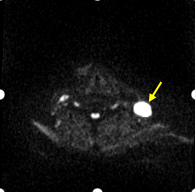

弥散成像显示左颈部转移淋巴结:

DWI图像

ADC图